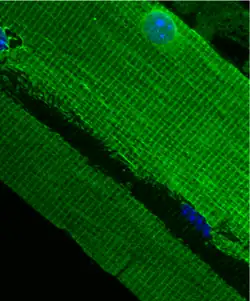

El costámero es un componente estructural y funcional de las células del músculo estriado[1] el cual conecta el sarcómero del músculo a la membrana celular.[2]

Los costámeros son complejos proteicos del subsarcolema alineados en la circunferencia de los discos z de las miofibrillas periféricas. Unen físicamente los sarcómeros, que generan la fuerza, con el sarcolema en las células del músculo estriado. Sin embargo, son considerados uno de los muchos tendones de Aquiles del músculo esquelético, ya que es un componente crítico en la morfología del músculo esquelético. Se cree que su compromiso está involucrado en una serie de miopatías.[3]